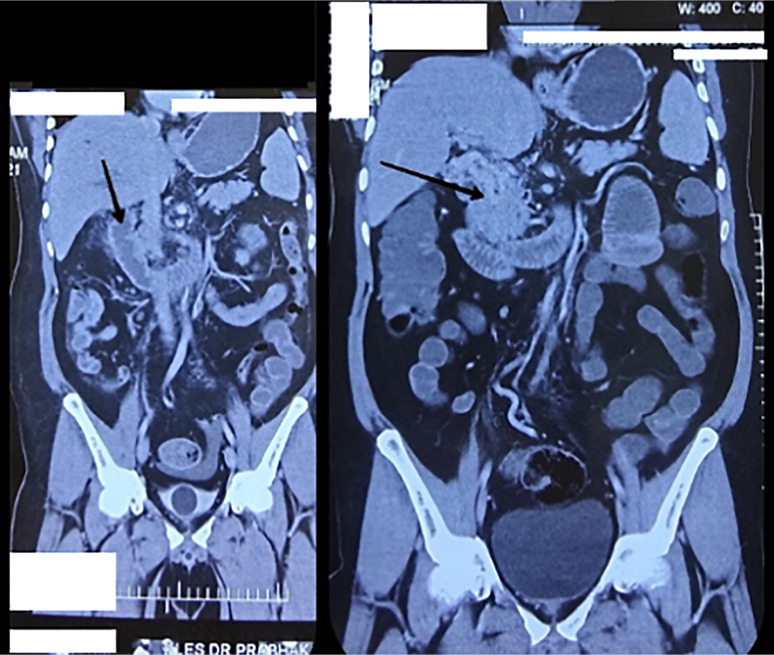

Case presentation: A male patient in his early 40s presented with 15 days of progressive upper abdominal pain and one day of vomiting. He had a history of diabetes and hypertension. Examination revealed tachycardia and epigastric tenderness. Laboratory tests showed neutrophilic leukocytosis and positive occult blood in the stool. Contrast-enhanced CT (CECT) revealed PVT extending into its right branch, jejunal wall thickening, and mesenteric engorgement suggestive of ischemia. Upper GI endoscopy showed esophageal varices and portal hypertensive gastropathy. He was managed conservatively with anticoagulation and discharged. One month later, he returned with recurrent vomiting, worsened by solid food. Repeat CECT showed jejunal obstruction with a 3-cm stricture. Exploratory laparotomy revealed dense adhesions; adhesiolysis, bowel resection, anastomosis, and feeding jejunostomy were performed. Histopathological examination showed a sealed-off perforation with acute suppurative inflammation and fibrotic changes consistent with ischemic stricture.